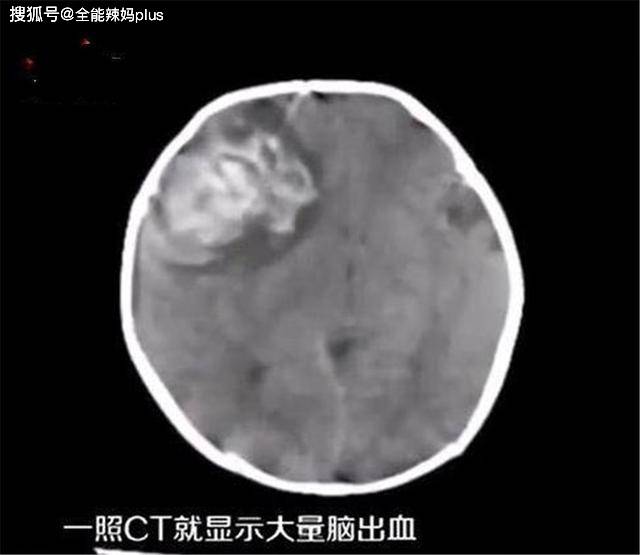

前不久 , 一名两个月左右的婴儿 , 口腔内突然出血不止 , 不停哭闹 , 家长赶紧把孩子送到了医院 , 结果做了一番检查 , 发现孩子有颅内脑出血的情况 。

殊不知正是因为这错误的风俗 , 竟然让孩子小小年纪就出现了脑出血的情况 。

虽然最后经过手术抢救 , 这名两个月的婴儿的命是保住了 , 但是后续需要经常来医院复查 , 并且这名婴儿日后患脑梗塞 , 脑出血等疾病的可能性比其他人要大得多 。